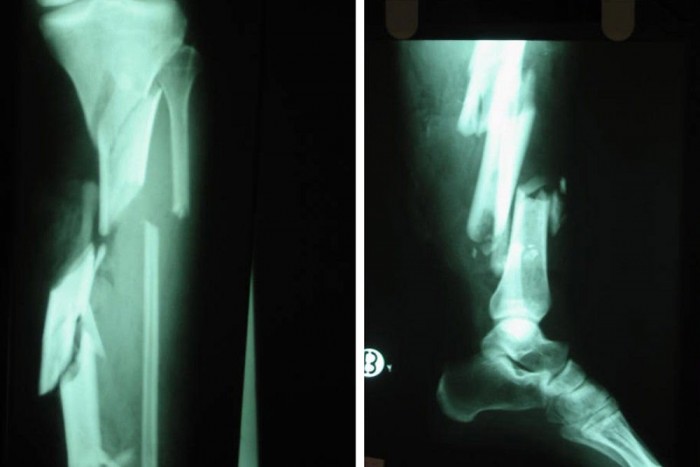

Az ütközés általában oldalról éri a gyalogost, ekkor először az autó felőli láb – túlnyomórészt a térd – eltörik, a másikon az energia függvényében szintén törés, vagy szalagsérülés keletkezik.

Már eddig is elég sokkoló események történtek szegény gyalogossal, de még mindig nincs vége. Az ütközés után a test elrepül, a gyakori halálos sérülést gyakran a betonra való csapódás okozza. A sérülés mértéke nagyban függ az autó sebességétől. 20 km/óránál megúszhatjuk egy lábtöréssel, 50 km/óránál viszont nem sok esély marad a túlélésre. Természetesen az sem mindegy, hogy az áldozat egy huszonéves sportos férfi, vagy egy csontritkulásban és számtalan betegségben szenvedő idős ember.